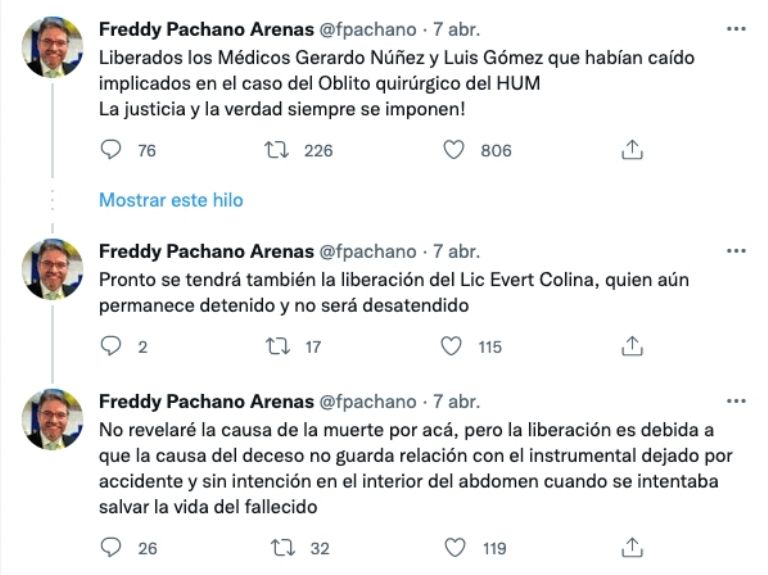

Un colega de ellos en el Hospital Universitario de Maracaibo, el doctor Freddy Pachano Arenas, ha dado seguimiento puntual al caso a través de su cuenta de Twitter e informó que no se trataba de un caso de negligencia, ya que ningún médico de forma consciente le haría daño a su paciente. «En las cirugías hay muchos riesgos, inherentes a la enfermedad y al entorno donde se trabaja, pero nadie quiere causarle daño al enfermo», escribió el pasado 1 de abril.

Pachano Arenas dijo que aunque no es constante, sí se han dado casos en los que se pueda dejar material quirúrgico dentro de los pacientes, aunque en este caso detalló que eso no fue la causa de muerte de Iván, ya que tras haber llegado al hospital para ser operado del colon, eso hacía que tuviera el abdomen delicado, lo cual, sumado a que era hipertenso y tenía daño renal, comprometía su estado de salud desde el inicio.

A raíz de sus tuits, muchos inetrnautas le cuestionaron que estaba tratando de encubrir la mala praxis de sus compañeros, pero él insistió en que el hecho de que los médicos le hayan dejado dentro al paciente el instrumental quirúrgico no era justificable; aún así volvió a mencionar es que eso no había sido la causa de fallecimiento del hombre y sí su deteriorado estado de salud.

El 7 de abril, Freddy Pachano informó que Gerardo Núñez y Luis Gómez ya habían sido liberados y que Evert Colina estaba pronto a salir libre. «Imposible culpar a alguien de homicidio intencional en un acto que busca salvar la vida de un ser humano», dijo. Hasta ahora no se sabe si la familia del paciente fallecido continuará con algún proceso legal por su muerte en el hospital, según 3eravoz.